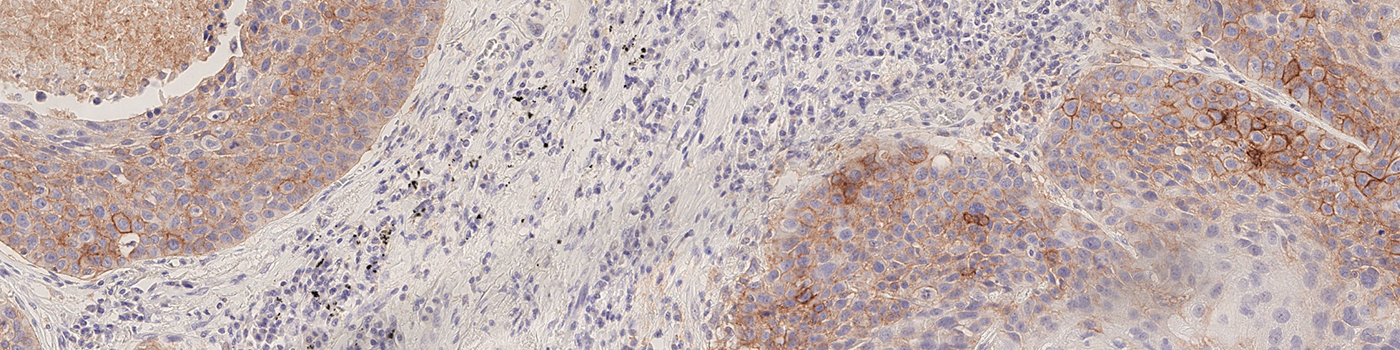

Immunotherapies directed at programmed death ligand 1 (PD-L1) and its receptor (PD-1) have enhanced the survival rate of a group of patients with advanced lung cancer. The expression of PD-L1 protein can predict which patients are more inclined to benefit from immunotherapy.

Our PD-L1 solution is fully automated and does not require manual input during analysis. The solution consists of four automated analysis steps. Once started, it automatically separates the patient tissue from control tissues and robustly identifies invasive cancer areas in the sample. Tumor cells are counted based on their PD-L1 expression and the resulting Tumor Proportion Score (TPS) for the whole tumor area is calculated.